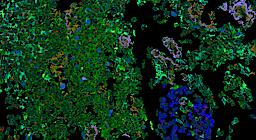

Pancreatic ductal adenocarcinoma is a lethal disease with limited treatment options and poor survival. We studied 83 spatial samples from 31 patients (11 treatment-naïve and 20 treated) using single-cell/nucleus RNA sequencing, bulk-proteogenomics, spatial transcriptomics and cellular imaging. Subpopulations of tumor cells exhibited signatures of proliferation, KRAS signaling, cell stress and epithelial-to-mesenchymal transition. Mapping mutations and copy number events distinguished tumor populations from normal and transitional cells, including acinar-to-ductal metaplasia and pancreatic intraepithelial neoplasia. Pathology-assisted deconvolution of spatial transcriptomic data identified tumor and transitional subpopulations with distinct histological features. We showed coordinated expression of TIGIT in exhausted and regulatory T cells and Nectin in tumor cells. Chemo-resistant samples contain a threefold enrichment of inflammatory cancer-associated fibroblasts that upregulate metallothioneins. Our study reveals a deeper understanding of the intricate substructure of pancreatic ductal adenocarcinoma tumors that could help improve therapy for patients with this disease.